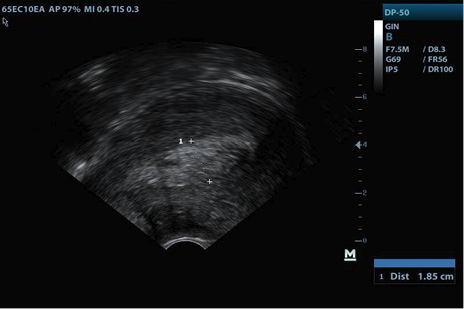

Consultó al médico ginecólogo en consulta privada, cuatro días después de la expulsión del producto, manifestando escaso sangrado y leve dolor pélvico; a su ingreso se encontró paciente tranquila, afebril, sin taquicardia ni taquipnea, abdomen blando, al examen con espéculo cérvix cerrado, escaso material sanguinolento en vagina, sin mal olor; en la ecografía se observó, como hallazgo positivo, endometrio irregular de predominio homogéneo con algunas zonas hipoecoicas, de 18,5 mm en corte longitudinal (Figura 1). Se ordenó cuadro hemático, GCH cuantitativa, evitar coitos y tactos vaginales, y se instruyó en signos de alarma.

Figura 1. Corte longitudinal de endometrio consulta inicial

Fuente: archivo personal del autor, con autorización de la paciente.